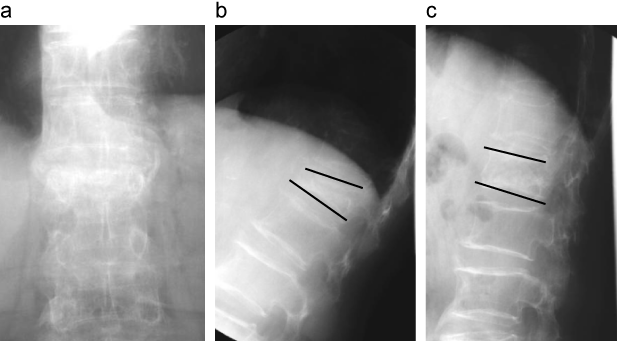

椎体骨折後骨癒合不全のX線画像

Vacuum cleftは過伸展位や仰臥位でのX線側面像で検出されやすい。

a:立位前屈位

b:仰臥位